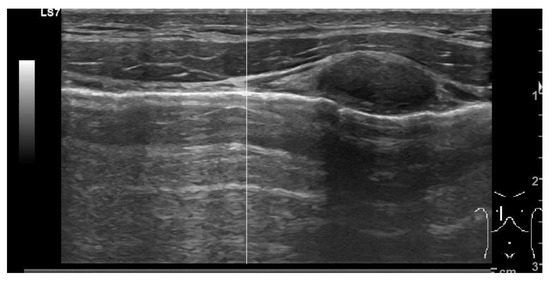

3.4.2. Tension Pneumothorax